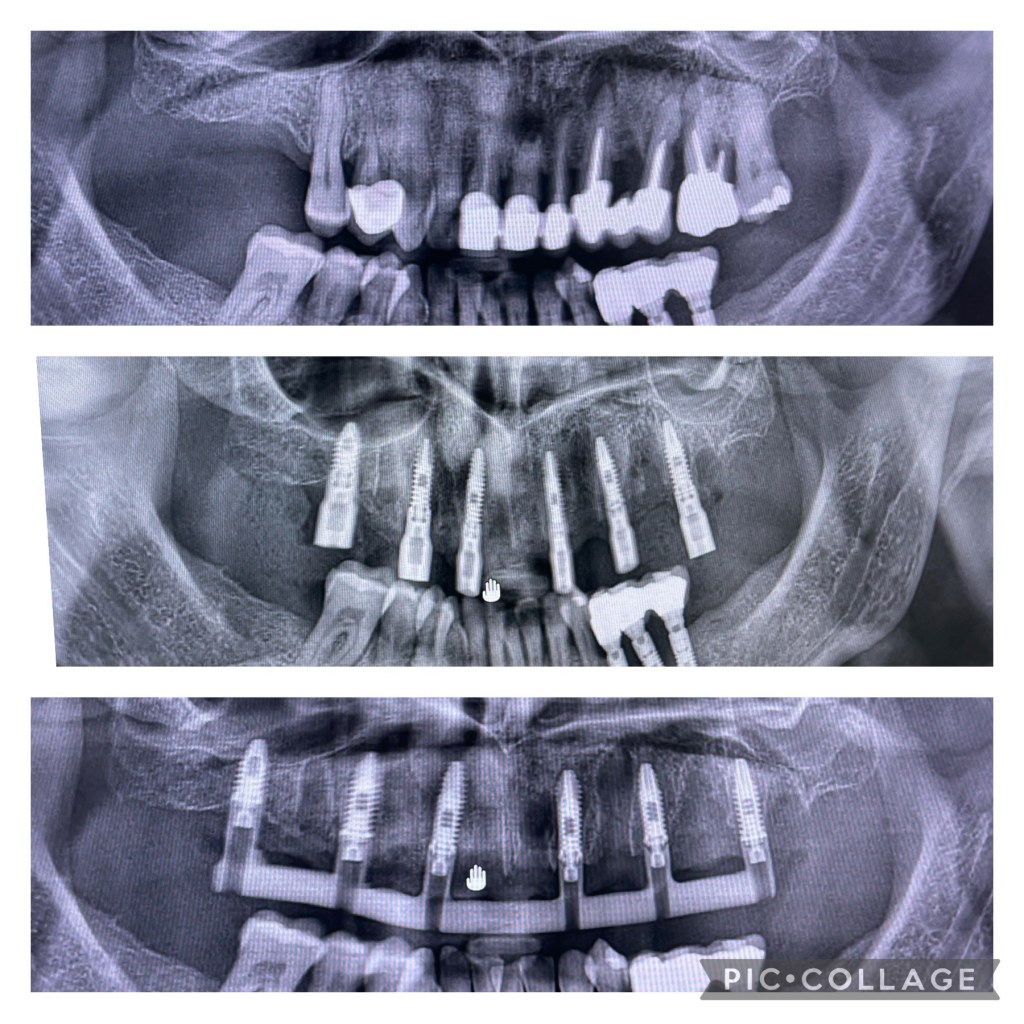

Caso clinico Carico Immediato

Realizzato dal Dr. Tolotti Alessandro con la collaborazione del laboratorio odontotecnico Dentalstyle

Caso clinico:

Bonifica dentale completa e contestuale inserimento di 6 impianti con chirurgia libera senza dime chirurgiche. Successivamente è stata provata una barra fresata e verificato il coretto accoppiamento con la fixture.

Dopo una prova estetica mediante prototipo avvitato che ha permesso di effettuare alcune valutazioni estetiche-funzionali, si procede alla consegna del manufatto protesico fisso avvitato.